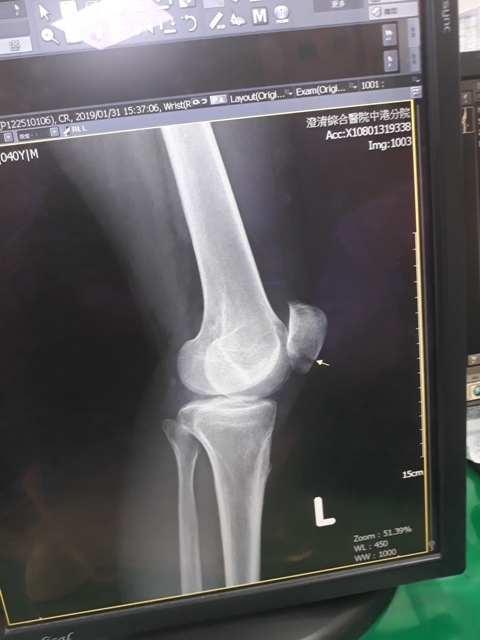

左腳X光↓

下午兩點初,爸媽從雲林來到台中,約三點半左右載我去澄清醫院。到達後先照了手和腳各兩張的X光,照完再至門診報到。骨裂後一段時間,當骨頭有感覺比較好時,很期待趕快去回診,想盡快知道我恢復了多少,但到了門診這天,原本應是期待的心情卻也參雜了些許不安的情緒。

進入門診前,我自認為手比腳恢復還快,因為比起一開始,手指比較能出力了,手腕可轉動的範圍也變大了。腳因一直用副木石膏固定住,不能動,所以也不知恢復多少。進入門診後,黃醫師說斷裂的骨頭都沒移位。手沒什麼進展(骨頭不會長那麼快),腳的部份下回再來復診時,可能會恢復的較快了。

左腳X光照↓

手沒什麼進展這件事,讓我比較吃驚,詢問黃醫師,手如果也改用副木,會不會比較好,黃醫師說,他個人是認為沒什麼差。他看著X光片照出來的結果,說開刀或不開刀他覺得都差不多。